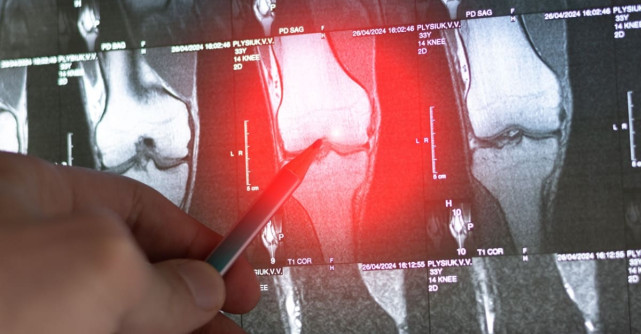

Simptome timpurii ale cancerului osos

Există anumite manifestări ale organismului ce ar putea indica posibila prezență a unor formațiuni tumorale la nivelul oaselor, aflate însă în stadiu incipient. Cancer osos - simptome dezvoltate precoce:

dureri de oase persistente: adesea, reprezintă primul semn al cancerului osos; pot fi localizate la nivelul osului afectat și se pot agrava noaptea sau în timpul unei activități fizice;

umflături sau sensibilitate: zona afectată poate deveni umflată sau sensibilă la atingere;

Simptome posibil produse într-un stadiu avansat

Pe măsură ce cancerul osos progresează, lista cu manifestări specifice acestei afecțiuni oncologice mai poate include:

fracturi patologice: oasele afectate pot deveni atât de vulnerabile, încât se pot fractura chiar și în urma unor traume minore;

deformări osoase: formațiunile tumorale pot provoca deformări vizibile ale oaselor afectate;